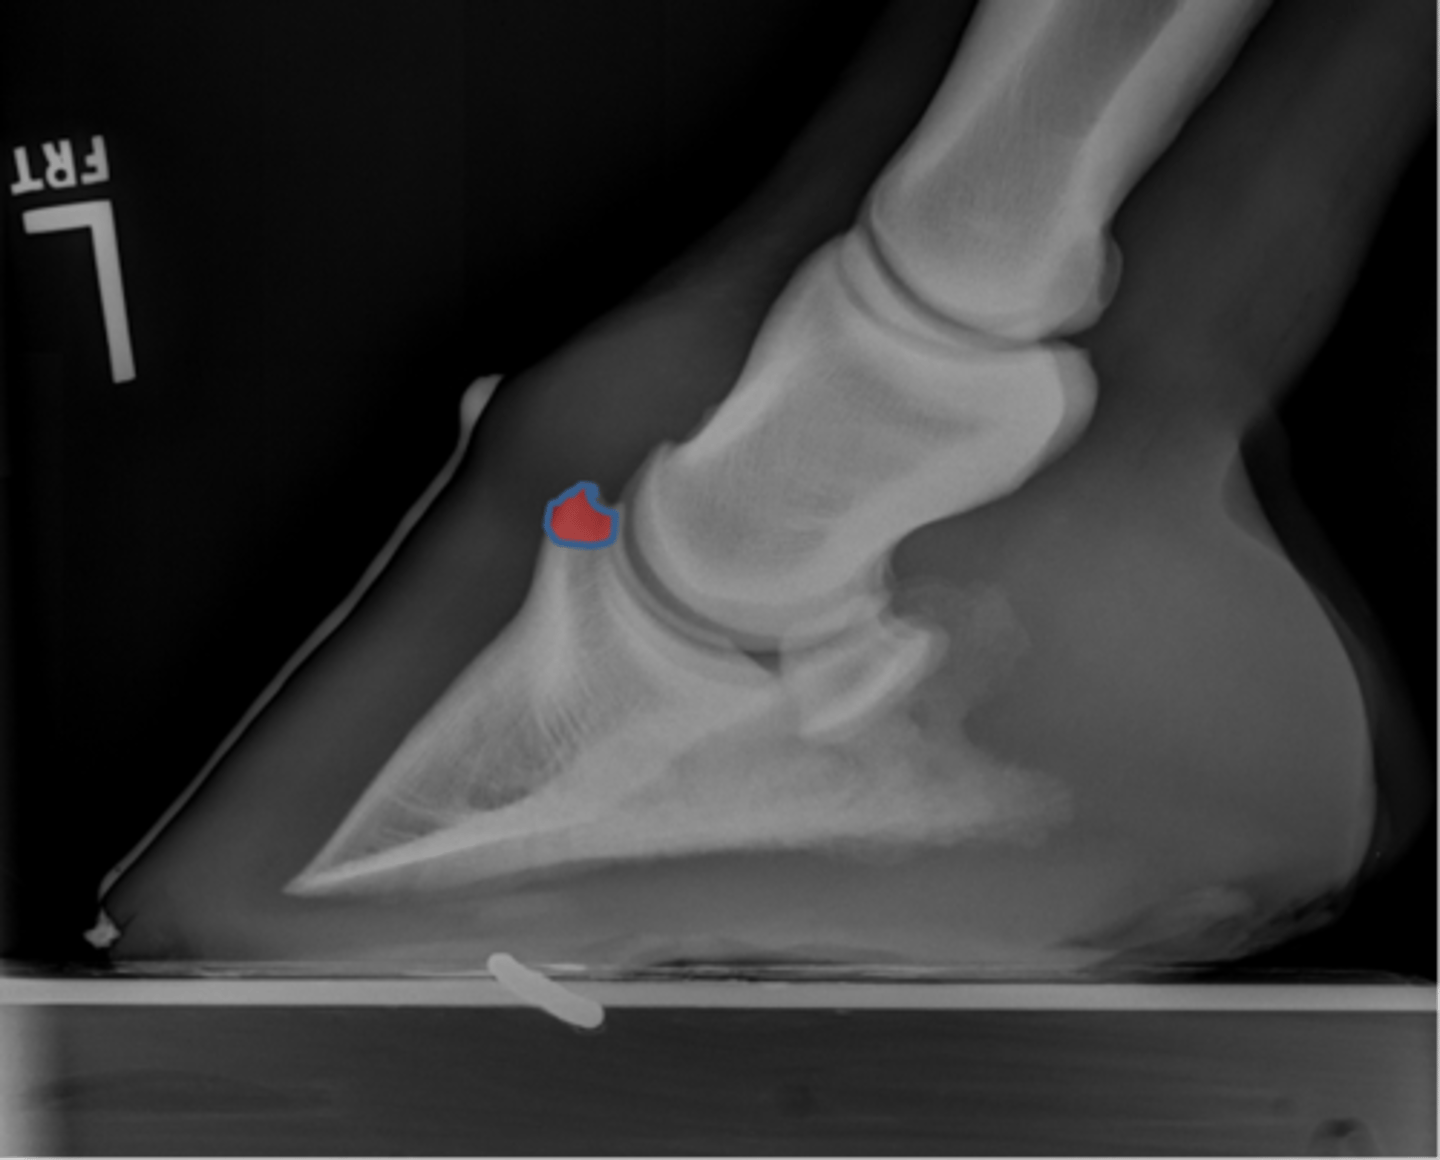

Coffin bone (P3)

Palmar process of P3

Extensor process of P3

Navicular bone

Proximal border

Flexor surface

Distal border

Articular border

Coffin joint

Short pastern (P2)

Coffin bone

Navicular bone

Crena

Vascular channelsv

Solar canal